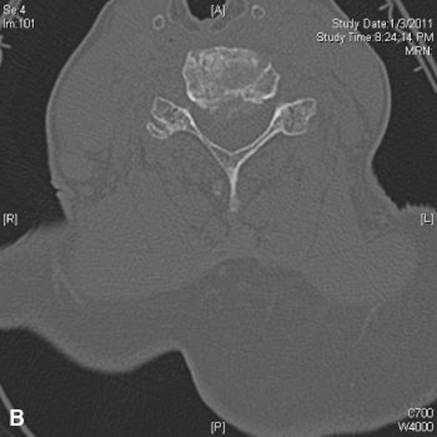

c. CT scan (Fig. 22.3A, B). It shows better bone detail than MRI, but is not as good at showing the neural structures. The two studies together are ideal for this group of patients, but this is obviously not cost effective, so MRI is the first choice.

FIGURE 22.3 Axial CT with soft tissue (A) and bone windows (B) demonstrating moderate to severe central canal stenosis secondary to an eccentric disc protrusion (C5–C6) as well as osteophyte with foraminal stenosis.